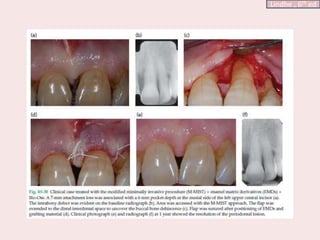

Modified-Minimally invasive surgical

technique (M‐MIST)

• The MIS (Harrel 1995) and the MIST (Cortellini & Tonetti 2007) include the elevation of

the interdental papillary tissues to uncover the interdental space, gaining complete access to

the intrabony defect, while in the M‐MIST (Cortellini & Tonetti 2009a) access to the defect

is gained through the reflection of a small buccal flap, without elevation of the interdental

papilla.

• The minimal flap reflection narrows the angle of vision and especially the light penetration

into the surgical field.

• The soft tissue manipulation during instrumentation requires more care since the flaps.

• Use of small instruments, like small periosteal elevators and tiny tissue players, is

mandatory for soft and hard tissue manipulation.

• Microblades, mini‐curettes, and mini‐scissors allow for full control over the incision,

debridement, and refinement of the surgical area, and sutures from 6‐0 to 8‐0 are mandatory

for wound closure.

Lindhe , 6th ed